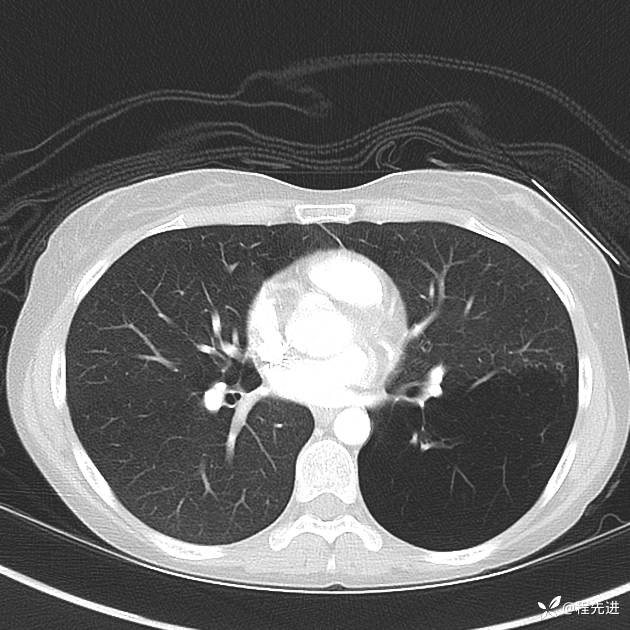

患者性别:女

患者年龄:25岁

简要病史:下胸部疼痛3天

CT增强: